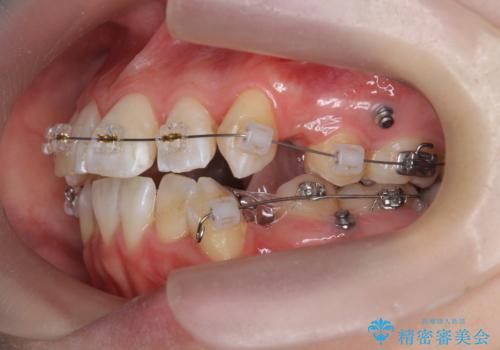

突き出た前歯を治したい 小臼歯抜歯+マルチブラケット矯正

- 矯正装置

- ワイヤー矯正

- 治療期間

- 2年8ヶ月

- 突き出て、気になる前歯の角度の改善を求めて来院されました。

前歯の角度を改善するために小臼歯4本の抜歯を行いワイヤー マルチブラケットを用いて、しっかりと前歯の角度を改善する治療計画としました。